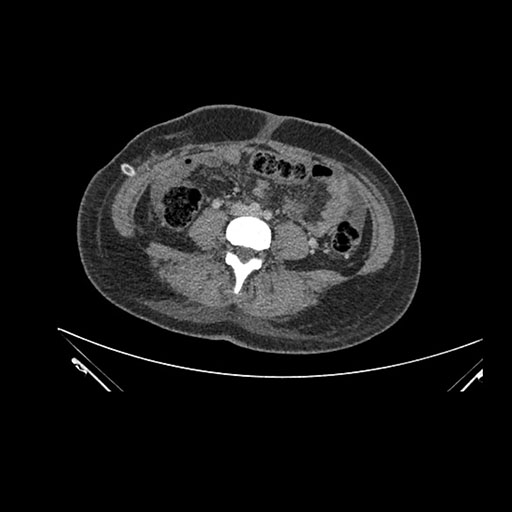

Imaging Analysis

Look through the patient's CT scan to identify any areas of concern for the necessary procedure.

Axial Venous

Based on initial findings, which issue(s) would you be most concerned about?